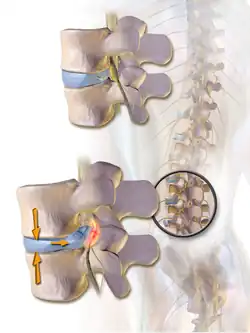

Une hernie discale est une lésion atteignant le rachis et caractérisée par le déplacement d'une partie d'un disque intervertébral hors des limites de sa situation normale. En principe, cette hernie est la conséquence d'une ouverture dans l'anneau fibreux laissant passer une partie du noyau pulpeux, plus mou, à l'extérieur de cet anneau. La hernie discale est habituellement en rapport avec une lésion dégénérative du disque liée à l'âge, pouvant être favorisée par un traumatisme ou des efforts répétés. Le plus souvent la hernie est localisée au niveau postérolatéral, ce qui est favorisé par la présence du ligament longitudinal postérieur dans le canal vertébral[1].

La hernie discale résulte habituellement de la progression d'une protrusion discale, c'est-à-dire une lésion incomplète de l'anneau fibreux permettant une saillie intermittente, selon les contraintes exercées sur le disque. Cette saillie est permanente lorsque survient la hernie.

La hernie postérieure est favorisée par la compression de la portion antérieure du disque lors de la flexion antérieure du tronc, ce qui entraîne la poussée du noyau pulpeux contre la portion postérieure de l'anneau fibreux. Ceci peut aboutir à la rupture de l'anneau fibreux et au déplacement progressif du contenu du noyau pulpeux à travers cette lésion vers le canal vertébral. La compression d'un nerf spinal du fait d'une hernie entraîne des symptômes décrits plus bas.